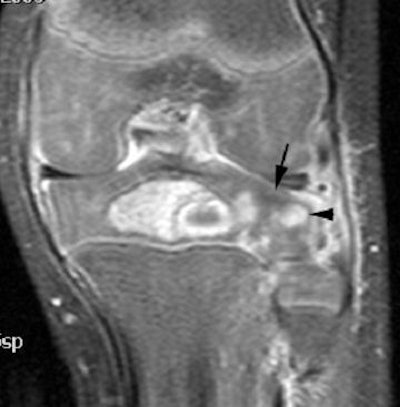

| Image of a 2-year-old with a final clinical diagnosis of proximal tibial epiphyseal osteomyelitis. T1 postgadolinium coronal sequence demonstrates surgically proven intraosseous abscess with diffuse epiphyseal osteitis, surgically proven, with adjacent focal epiphyseal cartilaginous perfusion abnormalities (arrow) and globular areas of abnormal enhancement (arrowhead). Image courtesy of Children's Hospital at Vanderbilt. |

"It is important not to confuse abscesses and perfusion defects despite their similarities, because abscesses must be treated surgically, whereas perfusion defects alone can be followed up over time," Johnson said.